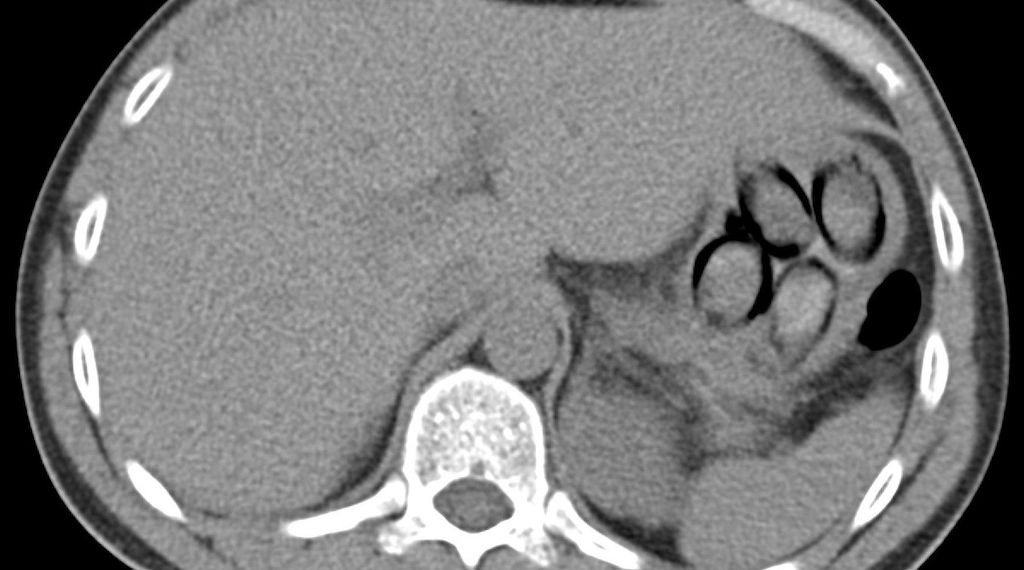

Kölner Zoll stellt Niederländer mit Kokain im Körper - (Foto: Röntgenbild zeigt mehrere Kokainpäckchen im Magen des Niederländers (Archiv))

Der Kölner Zoll hat am Flughafen Köln/Bonn einen niederländischen Reisenden mit Kokain im Magen festgenommen. Bei einer Kontrolle am 4. November am Fernbusbahnhof war ein 38-Jähriger aus Den Haag durch widersprüchliche Angaben, nervöses Verhalten und minimales Gepäck aufgefallen, wie das Hauptzollamt Köln mitteilte. Ein Drogenwischtest an den Händen des Mannes schlug positiv auf Kokain an. Eine Röntgenuntersuchung in einem Kölner Krankenhaus bestätigte den Verdacht: Im Magen des Niederländers waren mehrere Drogenpäckchen zu erkennen.